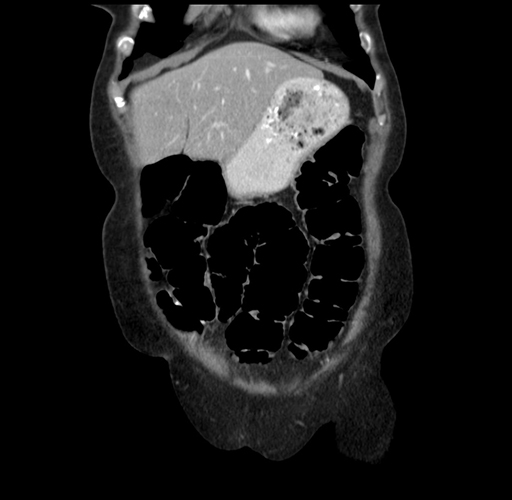

Pre-Chemo: Coronal Venous

Coronal Venous